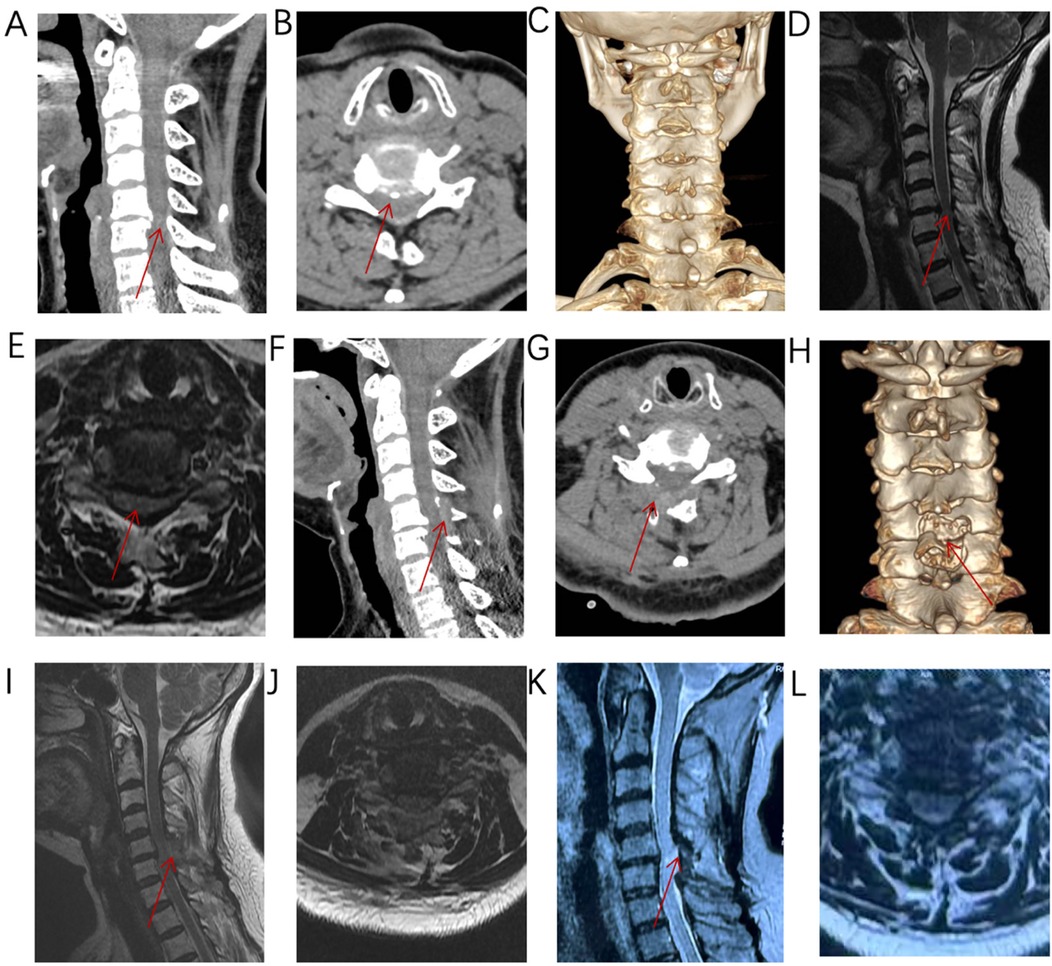

Take a patient with C5/6 “cervical spondylotic myelopathy, cervical spinal cord degeneration” as an example to introduce the surgical procedure. The patient is a 60-year-old woman admitted to the hospital for “numbness and pain in both upper limbs and difficulty walking for 3 months”. Combined with the patient's cervical CT and cervical MRI (Figures 2C–G), the diagnosis is “pinching cervical spondylotic myelopathy”. Cervical flexion-extension radiographs showed no cervical instability (Figures 2A,B), and the cervical curvature is 13.11°, with no cervical kyphosis. Surgical plan: Modified arcocristectomy under cervical posterior unilateral biportal endoscopy (UBE) for unilateral approach to bilateral decompression. The surgical steps are divided into: positioning, incision, establishing the working channel, building the working space, cavity creation, exposure of the contralateral lamina, lamina resection, ligamentum flavum resection, placement of drainage tubes, and suturing.

7. Excision of the ligamentum flavum, placement of drainage tubes, and suturing: The resection of the ligamentum flavum should be performed after the laminectomy is completed to reduce bleeding. After the decompression, good pulsation of the dura mater can be observed, indicating adequate neural decompression (Figures 1D, 4H,I). Postoperative imaging shows sufficient spinal canal decompression, with the decompression range of the inferior vertebra exceeding 1/2 (Figures 2F–J, 4H,I). A drainage tube is routinely placed after surgery, with the drainage bag under negative pressure. The drainage tube is removed on the first postoperative day, and cervical anteroposterior and lateral views, cervical CT, and cervical MRI are reviewed to assess the surgical outcome.

A series of medical images depicting different views of the cervical spine in axial, sagittal, and 3D reconstructions. Red arrows point to specific areas of interest, likely indicating abnormalities or features of medical relevance across the images labeled A to L.

Figure 2. (A–E) Imaging reveals anterior and posterior compression at C5/6, consistent with the diagnosis of pinching cervical spondylotic myelopathy. (F–J) Postoperative imaging shows adequate decompression, with the inferior lamina decompression range exceeding half of the lamina. (K–L) MRI imaging at 10 months after surgery shows that the spinal cord decompression is sufficient.